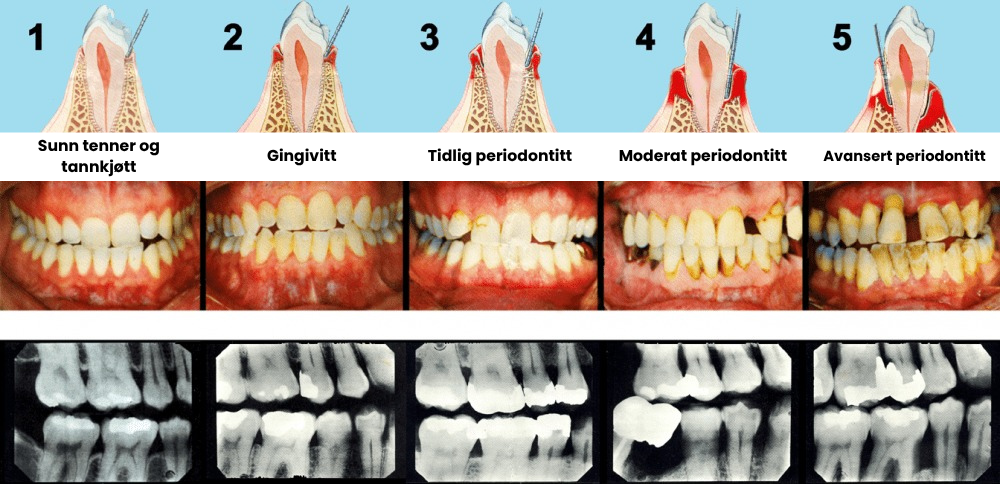

Hvis du har svart "ja" på noen av disse spørsmålene, har du tilbaketrukket tannkjøtt, også kjent som gingival resesjon, et vanlig problem i munnhulen som er preget av gradvis tap av tannkjøttvev som eksponerer tannrøttene.

Tilbaketrukket tannkjøtt oppstår når tannkjøttvevet trekker seg tilbake eller slites bort fra tennene, slik at de følsomme tannrøttene blir blottlagt. Denne tilstanden er mer enn bare et kosmetisk problem, den gjør tennene utsatt for karies, infeksjon og til og med tannløsning hvis den ikke behandles. Når tannkjøttet trekker seg tilbake, dannes det "lommer" eller mellomrom ved tannkjøttkanten hvor bakterier samler seg, noe som gjør at tilbaketrekningen forverres over tid.